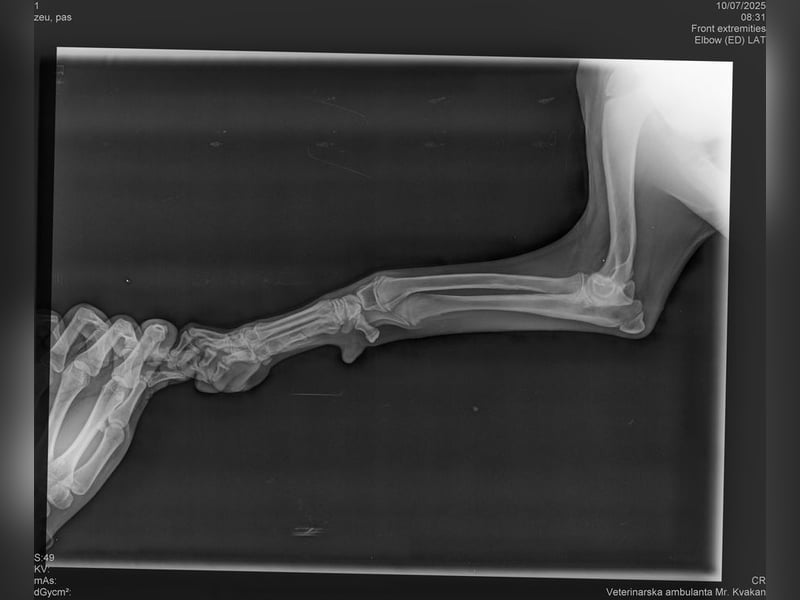

Bemerkungen: Unda humpelt ein wenig. Es sind Röntgenbilder vorhanden und darauf ist nichts ungewöhnliches zu erkennen. Momentan bekommt sie Schmerzmittel und die Angelegenheit wird Tierärztlich beobachtet

Die kleine Unda kam aus einer Romasiedlung. Wir konnten beobachten, dass sie ein wenig humpelt. Aus diesem Grunde durfte Unda im Tierheim einziehen. Sie wird nun tierärztlich überwacht. Die angefertigten Röntgenbilder lassen nichts ungewöhnliches an ihren Beinchen erkennen. Momentan bekommt Unda Schmerzmittel und die Angelegenheit wird weiterhin tierärztlich beobachtet